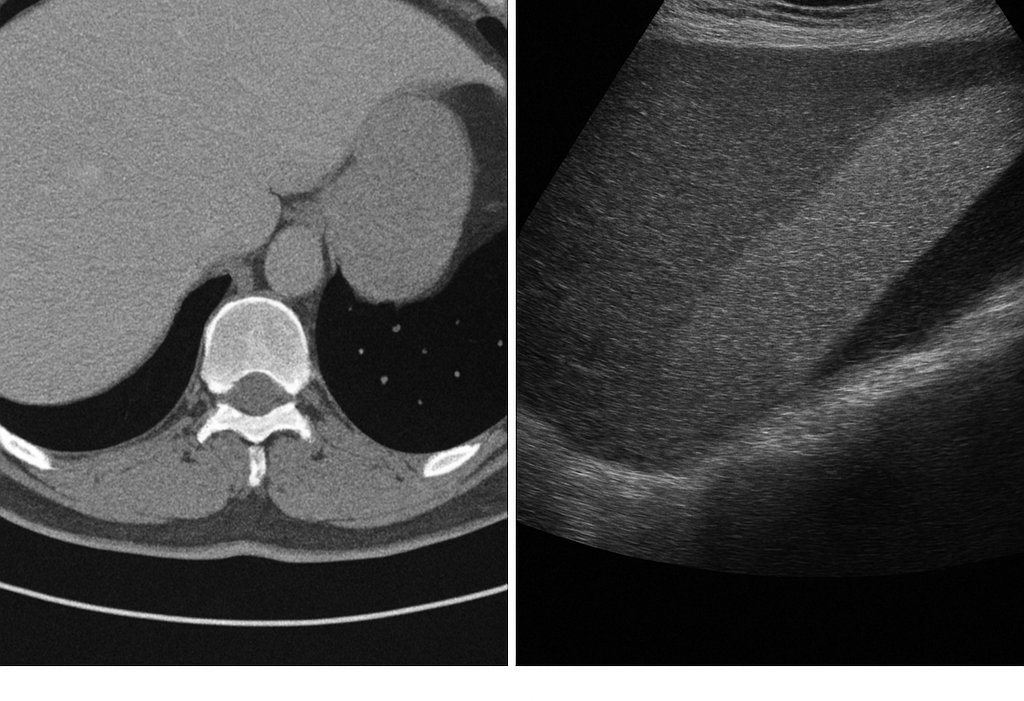

Image-2-Image Translation

For our research projects, we want to train and test DL networks for an automatic image-2-image translation, for example a conversion from CT to ultrasound and vice versa.

The topic is suitable for a bachelor or master thesis.

Please contact: saalfeldlab [at] gmail.com